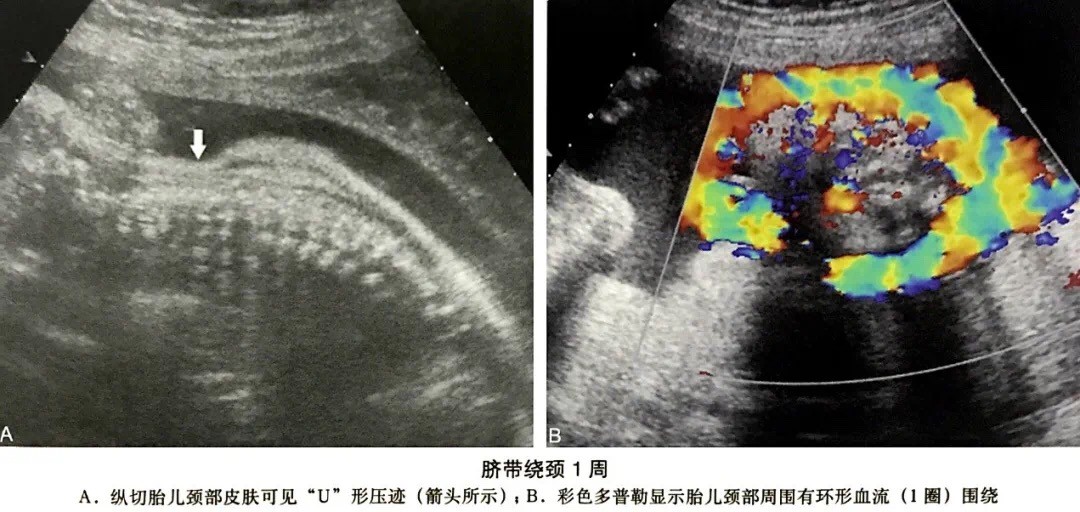

1、“U”型或“W”型压切迹,代表绕颈一周或二周。

最常见的绕颈1圈